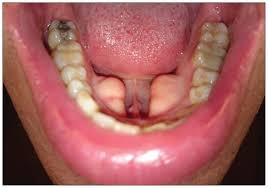

Fauces: The region at the back of the mouth that connects the oral cavity to the oropharynx; any swelling, discoloration, or lesions may signal underlying health issues.

Uvula: The small, fleshy extension at the back of the soft palate; variations in size and shape are typical among individuals.

Tonsils: Lymphoid tissues located on either side of the fauces; they can vary in size, often being larger in children and smaller or even absent in adults.